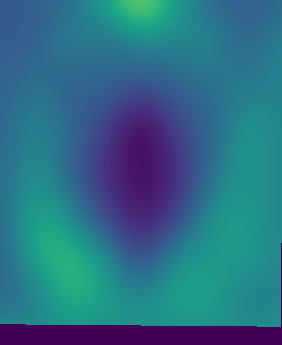

Figure 1: Reconstruction results for R = 3, with (1(a)) the fully sampled image, (b) the zero-filled image, (c) the reconstruction with no bias field estimation, (d) the joint reconstruction with bias field estimation using N4. The first three rows show reconstruction results for an HCP image, its zoomed-in version and the corresponding bias field. The next three rows show results for an in-house measured image. For visualization purposes, MR images are clipped to [0, 1.2] and bias fields, to [0.5, 1.8].

The quantitative improvement is also supported by the visual inspection of the images given in Figure 1. From the HCP image, one can observe that the level of artifacts is reduced with the proposed method. This becomes more evident in the zoomed-in images. The red arrow points to a part of the image where the proposed method can reconstruct the structures faithfully, whereas the baseline method struggles. Aliasing artifacts are globally suppressed better with the joint reconstruction method. Similarly, for the in-house measured image, the grey matter structure that the red arrow points to is not reconstructed in the baseline method, whereas it again appears with the proposed method.